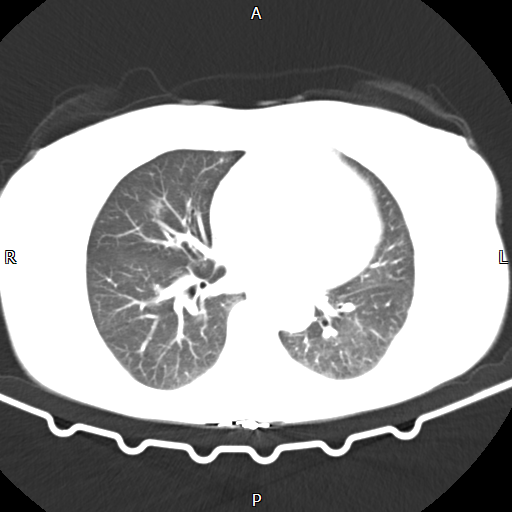

在重症监护室观察30多小时后,小刘转回普通病房。尽管性命得保,但术后第二关——“肺部感染”接踵而至。CT显示,历经创伤与手术,他的左肺萎缩成一团,胸腔充满渗出液。若不及时进行呼吸康复,积液极易演变为脓胸,导致严重感染。

术后第2天胸部CT提示左侧胸腔积液、肺不张

术后第10天胸部CT提示左侧胸腔微量积液,肺基本张开